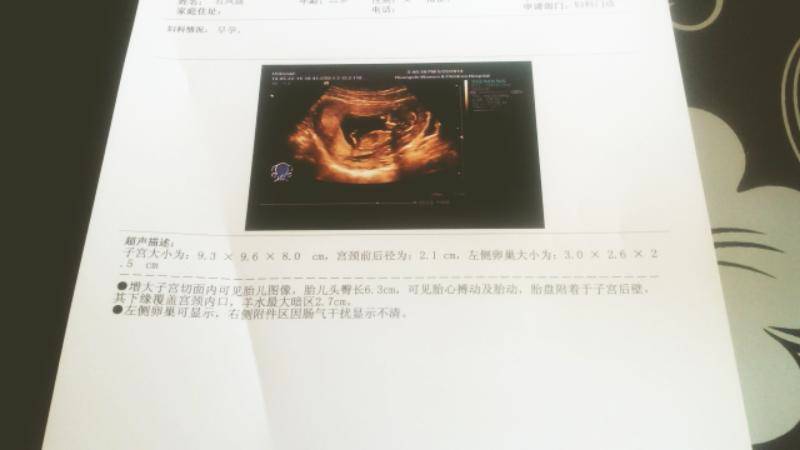

12周B超单,医生帮忙看看宝宝性别! 12周B超单,医生帮忙看看宝宝性别! 点击展开 じ★ve鴛荱芲埰sе璢瓈dе 2014-07-26 09:33 为您推荐: 其他回答 你好,根据B超报告单不能判断是男是女,只能通过B超动态观察胎儿性别。 张笑珠 2014-07-26 09:33 相关问题 四个月宝宝B超照 请医生帮忙看看 有谁可以看出性别的? 我怀孕是周了到现在还没有吃过叶酸、因为宝宝还小、要半个月后照b超、问医生要不要吃什么、她说什么也不 孕30周刚做了b超没赶上,医生下班了,麻烦帮忙看看洋水正常吗,还有胎盘已经2级了正常吗,胎盘位置会